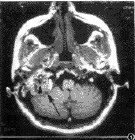

由於本病出血較為兇猛,一旦懷疑本病,不應進行活檢,應先行影像學檢查。顳骨高分辨CT掃描對頸靜脈鼓室球瘤的診斷、病變範圍的判定有重要價值,鼓室球瘤的早期常表現為鼓岬表面的軟組織影,局限於鼓室內。後期常向乳突、耳咽管、外耳道發展,表現為外、中耳的腫物影。頸靜脈球瘤早期表現為頸靜脈孑L擴大,邊緣不規則,晚期頸靜脈孑L邊緣出現“蠶食樣”改變,腫瘤向上侵入鼓室、鼓竇,向下侵蝕頸靜脈和顳下窩,向內侵犯面神經骨管,巨大的頸靜脈球瘤可侵入顱後窩至腦內,乙狀竇、頸靜脈球常受壓侵蝕,亦可包繞頸內動脈周圍。MRI表現為頸靜脈孑L區軟組織,T.WI為低信號,T:WI為明顯高信號,注射增強劑後腫瘤呈明顯的不均勻強化。並可見特徵性的“撒胡椒麵表現”。磁共振血管造影術(MRA)可初步了解腫瘤周圍的頸內動脈、頸外動脈、頸內靜脈、乙狀竇等大血管情況 。